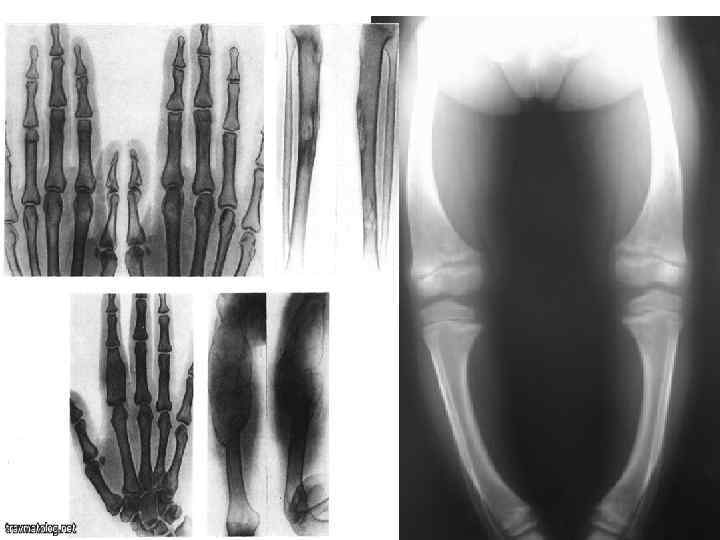

Визуальные материалы, связанные с болезнью Горхема-Стаута

Раздел: Альбом открытий